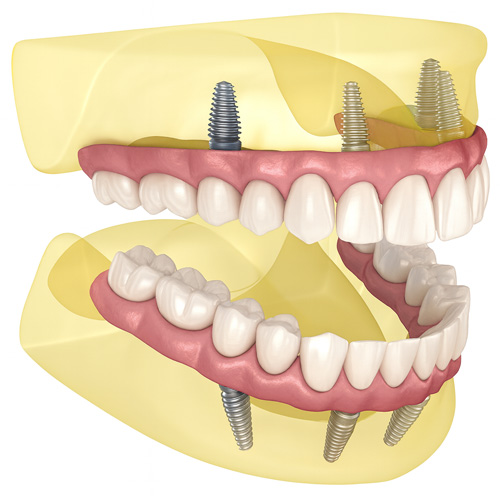

わずか4本のインプラントで、片顎すべての人工歯(フルアーチ)を支える固定式の治療法です。

従来の総入れ歯や多数のインプラント治療と比べて、手術負担を減らしつつ、しっかり噛める固定式の歯を短期間で実現できるのが特徴です。

| 埋入角度 | 奥の2本を斜め(約30〜45°)に埋め込み、骨量を有効活用 |

| 固定方法 | 4本のインプラントに連結バーを介し、ブリッジ型の人工歯を固定 |

| 適応症 | 多数歯欠損、無歯顎(上下いずれかの歯がほぼない状態) |